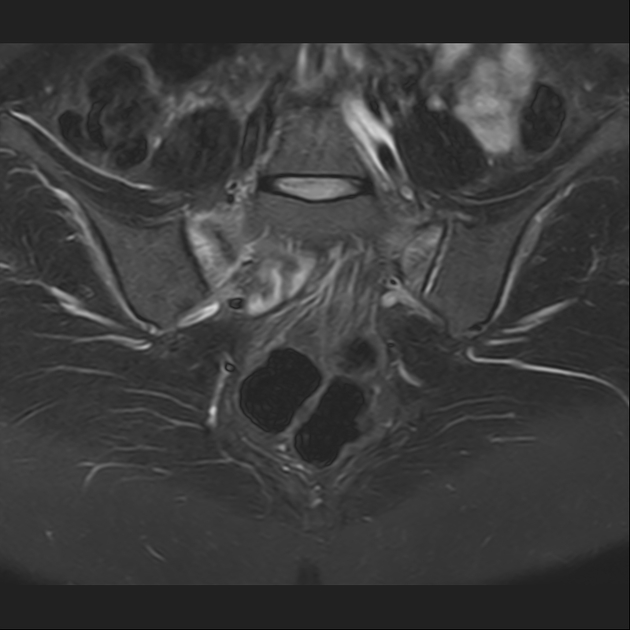

磁共振检查:

T2

2、单侧或双侧骶骨翼骨皮质断裂,见迂曲纵行骨折线,大致与骶髂关节平行(双侧多见);

3、骶骨体部看见骨折线

4、冠状位上述骨折形成 “H”型 ,故有人称东风本田征(为了方便记忆)

6、磁共振上可以发现骨折线周边明显的骨髓水肿,增强扫描明显强化

磁共振影像表现